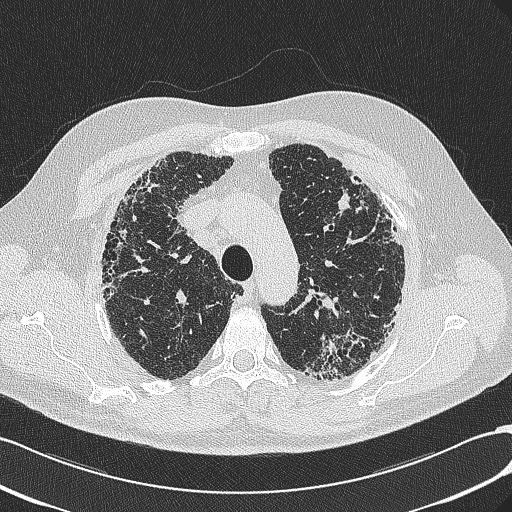

我在图像1上使用阈值掩码(图2)创建了以下图像(图3)。我试图使用opencv将图像3(肺)中央图像之外的所有像素转换为一种颜色(例如黑色)。基本上,这样我就只能在一个均匀的背景下(甚至是透明的)看到肺部的图像。我的问题是外部像素和图像3中肺内像素的相似性。这能用opencv吗?